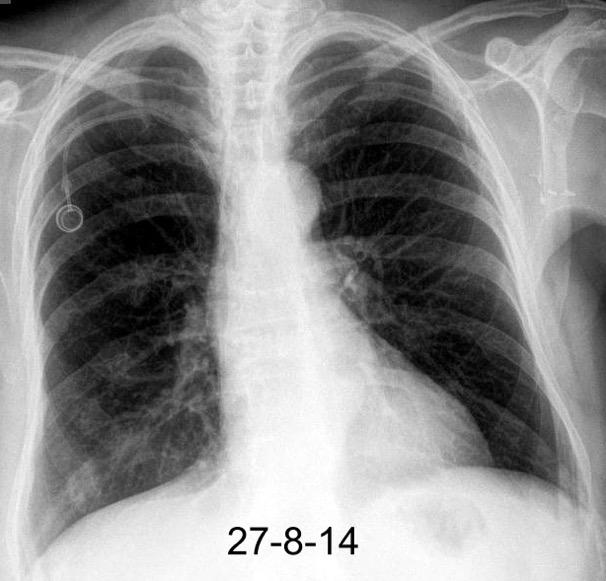

Hodgkin clásico de esclerosis nodular.

Adenopatías región cervical y mamaria interna, prevasculares y VAP. Doble contorno aórtico.